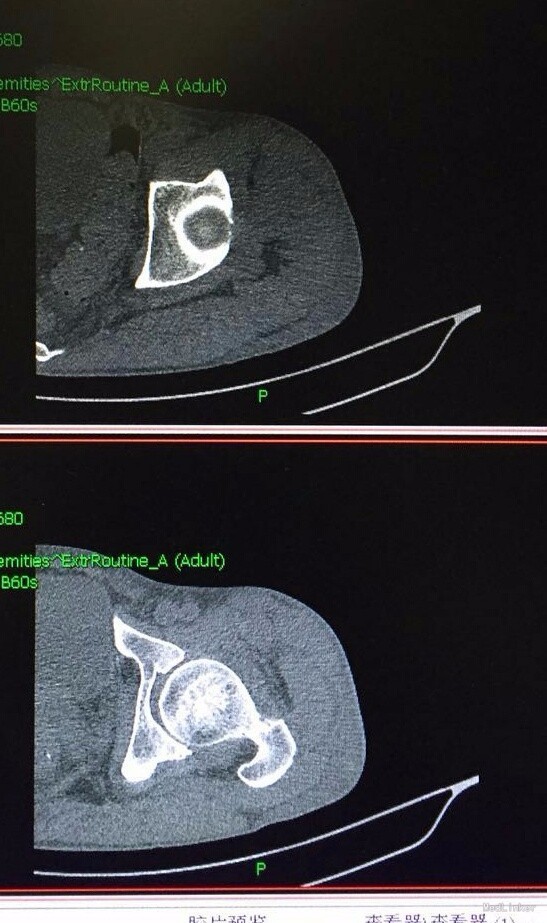

患者男,45岁,因“左髋部摔伤五日余”入院。 患者自诉于五日前步行时不慎摔伤,左髋部着地,伴疼痛,活动受限,遂求治于当地医院,行影像学检查示:左侧股骨颈骨折,给予止痛制动及其他对症支持治疗,治疗后症状无明显好转,遂转入我院,门诊以“左侧股骨颈骨折”收入院。 患者摔伤以来,精神睡眠饮食可,大小便正常,体力一般,体重无明显下降。 既往患者心衰史十余年,新功能三级,口服阿伐他丁、培哚普利、阿司匹林、螺内酯、速尿等控制病情;十年前行瓣膜置换术。其余无特殊。

查体:T:36,2℃,P:86次/分,R:20次/分,BP:135/80mmHg。神志清楚,查体合作,面容正常,全身浅表淋巴结无肿大。心肺腹无异常,双下肢无水肿。生理反射存在,病理反射未引出。 专科情况:患者卧床,不能行走,脊柱生理弯曲存在,未及明显畸形,双上肢皮肤感觉运动可,右下肢皮肤感觉运动可,右髋压痛阴性,右膝压痛阴性,直腿抬高试验90度,四字征阴性,左下肢外旋畸形,较右下肢稍缩短,皮肤感觉可,左髋压痛阳性,左膝压痛阴性,直腿抬高试验及4字征因疼痛不能配合,双侧膝跳反射正常,巴氏征阴性,余生理反射存在,病理反射未引出。 辅检:外院影像学检查是:左股骨颈骨折。我院术前检查无异常,影像学检查见下图。

诊断:左大腿血肿,皮下水肿;心力衰竭(心功能3级) 治疗:止血、脱水、抗心衰、其他对症支持治疗。

这个病人应该是下面医院诊断错了,患者并没有骨折,在我院行止血,脱水等一般治疗。骨折的特有体征有畸形、异常活动、骨擦音或骨擦感,以上三种体征只要发现其中之一,即可确诊。临床症状和体征外,更有影像学检查结果可以确诊,所以骨折的确诊还是比较清楚容易的。